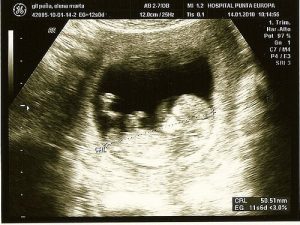

Ultraschall:

Das ist eine sehr gängige Methode. Schon früh erkennt der Arzt damit eventuelle Komplikationen. Gleichzeitig erhältst du damit das erste Bild deines Babys.

Auch das Geschlecht des Babys bestimmt der Arzt mittels Ultraschall. Im Falle einiger Anomalien, wie einem Herzfehler oder chromosomalen Abweichungen, erkennt man diese mit der Anwendung des Ultraschalls verhältnismäßig früh.

Sonografien oder Ultraschalluntersuchungen der zweiten Stufe führt man durch, wenn ein Verdacht auf eventuelle Geburtsfehler besteht.

Es ist eine nicht-invasive Technik, die mit einem Apparat ausgeführt wird, der Wellen erzeugt. Diese Wellen schaden dem Baby nicht, doch sie erlauben es, in die Gebärmutter hinein zu schauen.